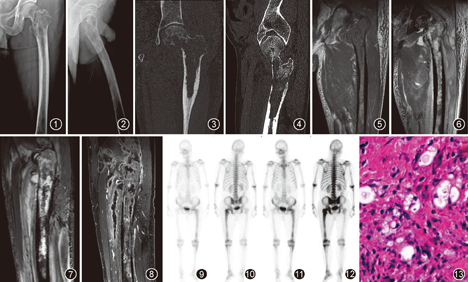

影像表现:X线示左侧股骨上段骨干、股骨颈不规则骨质密度减低,累及长度约9.3 cm,骨皮质变薄,未见骨膜反应,周围软组织肿胀、密度增高(图1, 图2)。CT平扫示左侧股骨上段骨干、股骨颈不规则骨质破坏,股骨头受累,局部骨皮质不连续,内可见小片状死骨影及少量硬化骨嵴,边缘可见轻度骨膜反应,周围软组织肿胀、密度不均(图3, 图4)。MRI显示病变范围较CT广,向下达左股骨中段,上下长约18 cm,骨髓腔内信号异常,T1WI、T1WI压脂呈不均匀等低信号;T2WI、T2WI压脂及质子密度加权成像(PDWI )均呈不均匀高信号;增强扫描呈不均匀强化,骨内外均可见多个大小不一的脓腔,呈环形强化,部分脓腔内见分隔(图5, 图6, 图7, 图8)。单光子发射性计算机断层显像(SPECT-CT)示病变区域血液灌注增加并核素浓聚,左股骨中下段及左膝关节弥漫性核素轻度浓聚(图9, 图10, 图11, 图12)。根据影像诊断为左股骨上段及软组织感染性病变。

术前诊断左股骨上段骨髓炎,行手术治疗。手术行左髋部平股骨大粗隆处及左大腿远端外侧分别切口,于股骨大粗隆及股骨下段外侧处开窗,见骨髓腔大量脓性黏稠分泌物,内可见大量死骨,以股骨内侧壁明显,左股骨近端骨质破坏明显,剔除死骨,将上下开窗处搔刮贯通,反复大量双氧水、生理盐水冲洗,术后留置引流管。

病理检查:左股骨近端纤维组织增生,大量炎细胞浸润并坏死,可见多核巨细胞及组织细胞并吞噬细胞现象。行阿尔辛蓝染色(AB)、过碘酸雪夫染色(PAS)及六胺银染色,可见孢子及荚膜;抗酸染色阴性,符合真菌性骨髓炎(图13)。